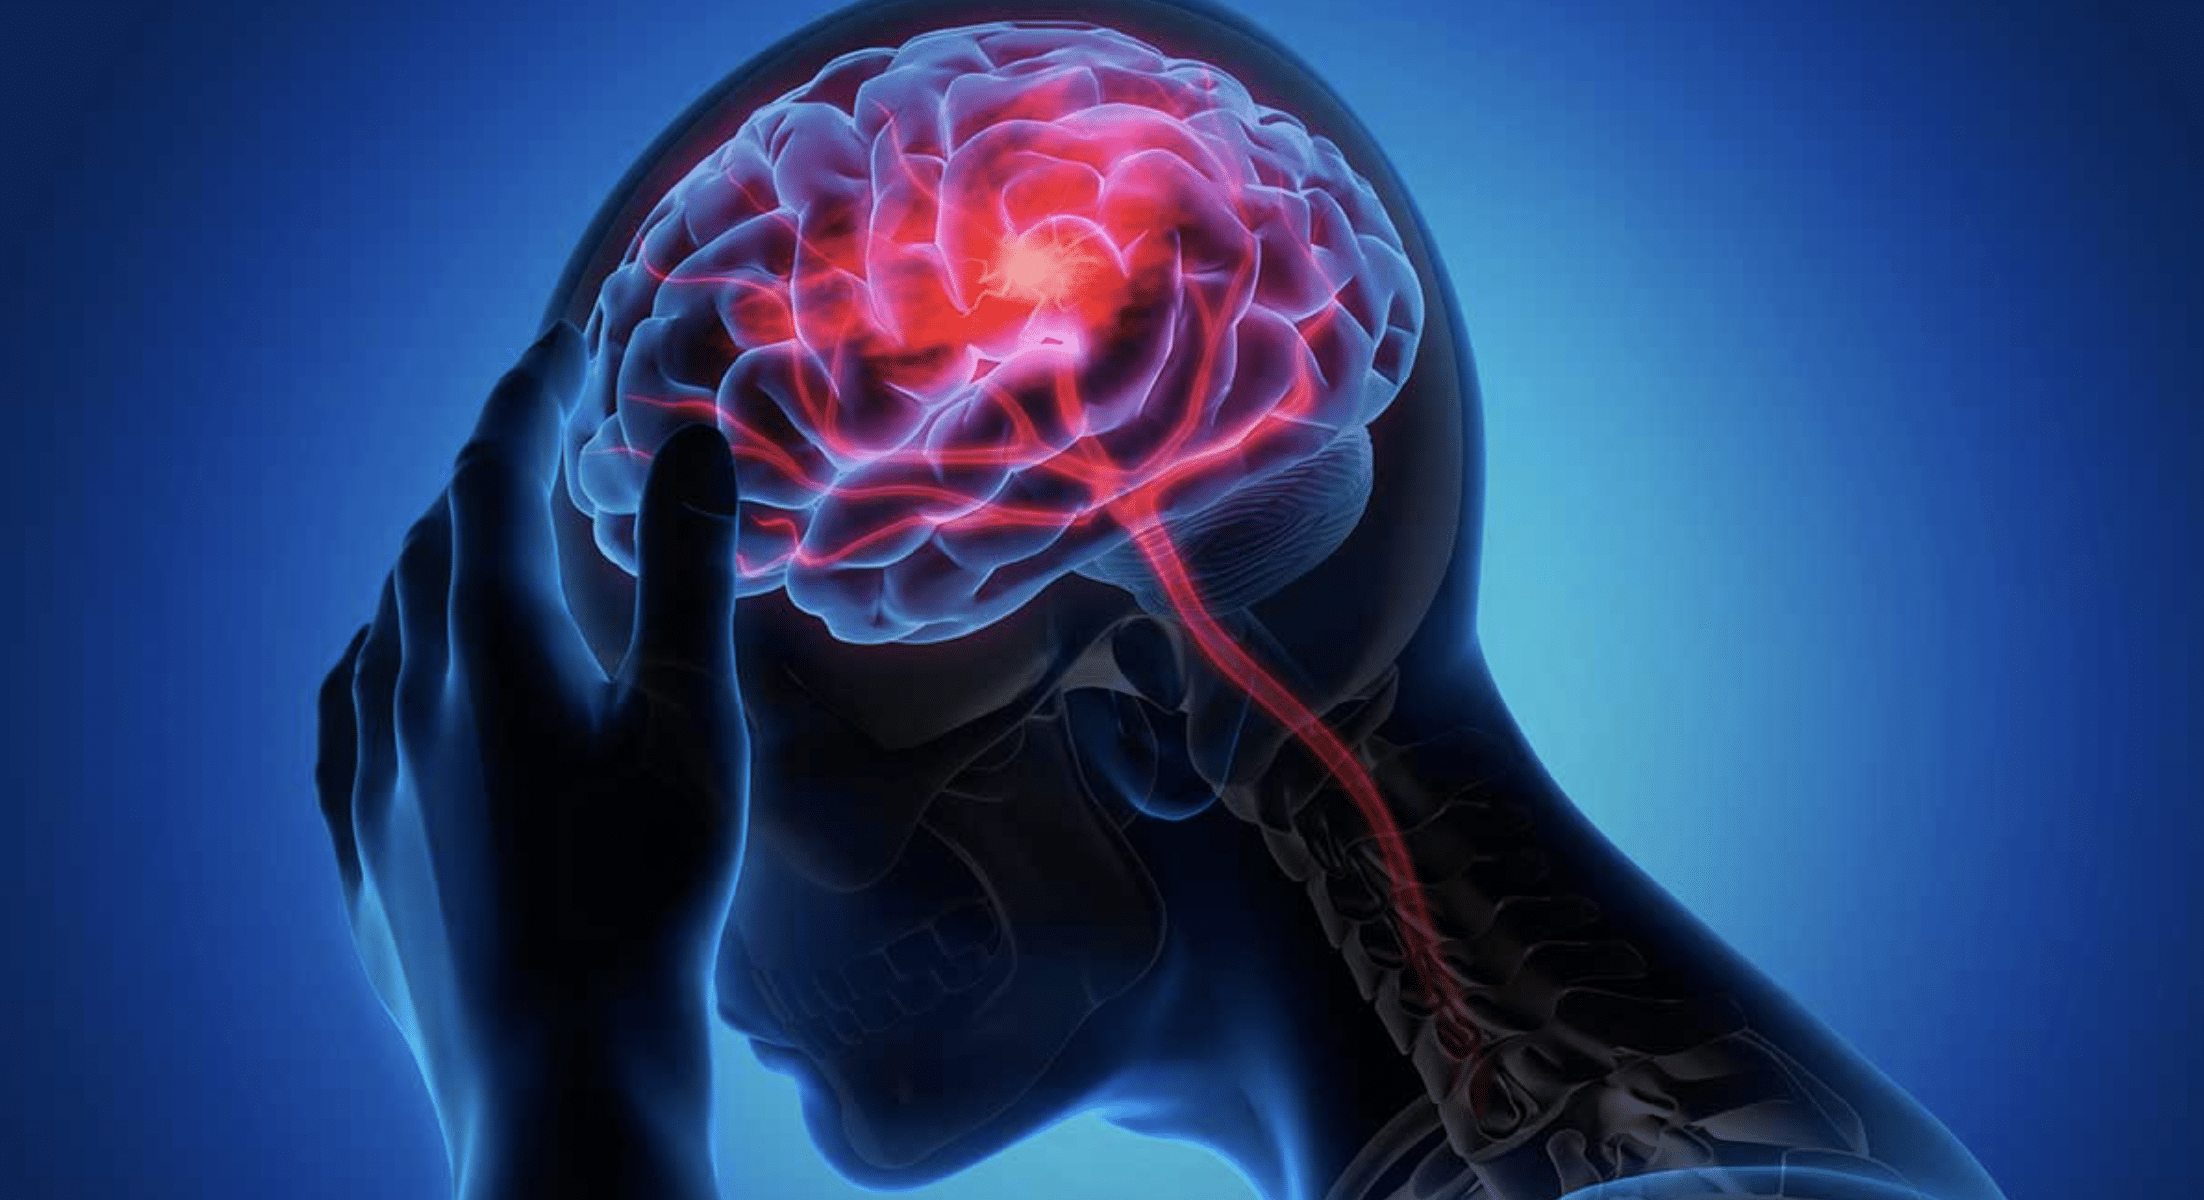

En México, el derrame cerebral se posicionó como la séptima causa de muerte, al registrar 37 mil 453 fallecimientosdurante el año 2021, de acuerdo con cifras del Instituto Nacional de Estadística y Geografía (Inegi). Este padecimiento afecta principalmente a hombres mayores de 65 años y, a nivel mundial, representa la principal causa de discapacidad en adultos.

Especialistas advierten que el mayor desafío no solo radica en la capacidad de atención médica, sino en el diagnóstico oportuno, pues el tiempo de reacción puede significar la diferencia entre una recuperación exitosa y un daño neurológico irreversible.

El derrame cerebral, también conocido como ictus, ocurre cuando el flujo sanguíneo hacia una zona del cerebro se interrumpe, ya sea por la obstrucción de una arteria o por una hemorragia interna. Esta falta de irrigación provoca que las células comiencen a morir en cuestión de minutos, afectando funciones motoras, del habla o cognitivas.

Las autoridades sanitarias explican que existen dos tipos principales de ictus:

- Isquémico: provocado por el bloqueo de un vaso sanguíneo.

- Hemorrágico: causado por la ruptura de una arteria dentro del cerebro.

Ante esta condición, el tiempo es el factor decisivo. Para la identificación temprana de síntomas, médicos recomiendan la estrategia “Camaleón”, que permite reconocer señales de alarma de forma rápida:

- Cara: debilidad o caída en la mitad del rostro.

- Mano: pérdida de fuerza en la mano o incapacidad para levantar el brazo.

- Lenguaje: dificultad para pronunciar palabras o hablar con claridad.

- Teléfono: ante cualquiera de estos signos, llamar de inmediato al 911 o acudir al área de urgencias del hospital más cercano.

Profesionales de la salud recuerdan que actuar en los primeros minutos puede reducir considerablemente las secuelas permanentes y salvar la vida del paciente.